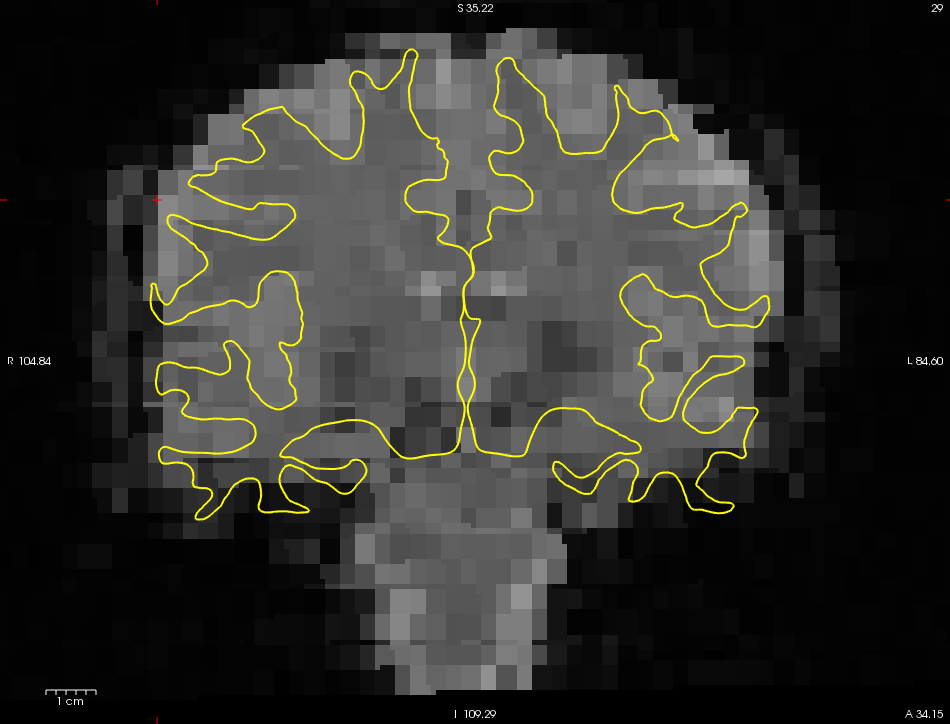

Masking

运行期间产生的Mask存放于masks目录之下。运行ls -ltr masks。(注意: ls -ltr masks 表明罗列出masks文件夹中的文件按照创建时间进行排列)您能够发现一个名称为brain.nii.gz的文件。他是通过使用FSL BET程序产生的二进制mask,还有一个由三个体素嵌入的mask名称为brain.e3.nii.gz的文件。这个eroded mask只能通过从脑组织中计算得到(减少边缘效应)。这些文件和template文件有着相同的维度。查看masks命令:

freeview -v template.nii.gz masks/brain.nii.gz:colormap=heat:opacity=0.75 -viewport cornonal

freeview -v template.nii.gz mask/.brain.e3.nii.gz:colormap=heat:opacity=0.75 -viewport coronal

您可以通过移动不透明的滑块或者输入一个新的值来调整mask的不透明度。现在,mask的不透明度设置的是0.75(这是通过在freeview的命令行中设置 opacity=0.75),这样您就能看到哪里与template的volume重叠。brain.nii.gz是用于约束体素的操作步骤。利用eroded mask计算强度归一化和全局平均时间过程的平均功能值。其他的masks之后会讲到。